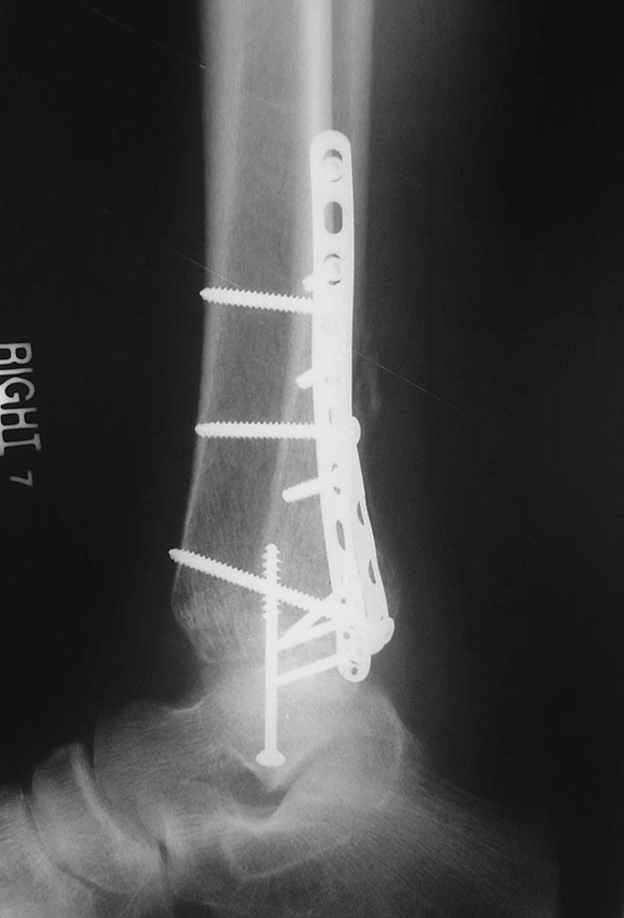

Отправитель: Djoldas Kuldjanov, M.D. 16 Сентябрь 2004, 22:00

Второй случай сделан из одного разреза

Дж

ЕЧ LISS plate, mininvasive approach - luxurous !

Вопрос практического характера - такой подход рутинный или при определенных показаниях и каких? Спрашиваю потому, что при потоке больных - закрытая голень, бедро, голеностоп и т.д. лучевая нагрузка должна быть немалая, каковы показатели дозиметра после такого операционного дня и при 2-3 операционных днях в неделю по 5-6 случаев (не считая ургентностей)?

С точки зрения : Сгорая сам - свети другим :-)) это вполне понятно, но личная практика показывает, что далеко не все пациенты относятся волнительно и критично к длине кожного разреза. Подозреваю, что это и есть критерий при выборе техники фиксации?

На прямой проекции послеоперационного Рг макроскопически все выглядит очень анатомично, при микроскопическом ( :-)) ) рассмотрении можно все-таки заметить вальгизацию тарана, суставная щель в латеральном отделе сустава несколько уже , чем в медиальном при отсутствии латерального смещения тарана. У меня был аналогичный случай (без LISS , без мини доступа) с вальгусным наклоном тарана при восстановленном ankle mortise при последовательном наблюдении с интервалами в 6-8 недель в послеоперационном периоде отмечалось прогрессирующее сужение суставной щели в латеральном отделе сустава, закончившееся посттравматическим ОА, к счастью боли умеренные, купируемые аналгетиками или своими эндорфинами:-))(активная пациентка, у которой нет времени на болезни....) Какова жизненная ситуация в приведенном вами случае? И последнее, что я хотел бы прояснить для себя - фиксация внутренней лодыжки: я обычно комбинирую фиксацию компрессирующим винтом со спицей - по идее ротационная стабильность должна быть лучше, чем один винт, каковы ваши наблюдения в этом плане?